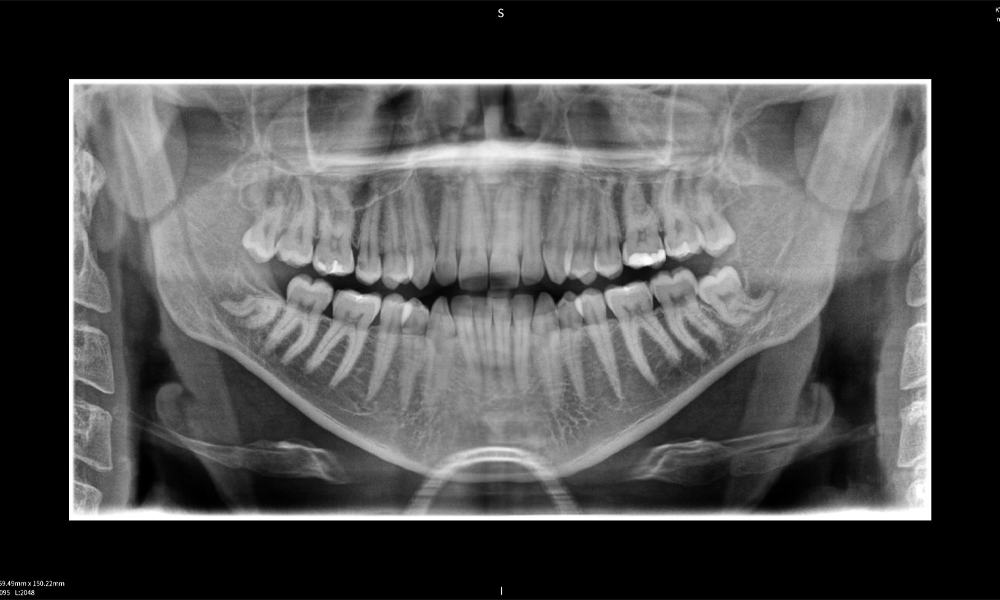

Figura c: Resultados de imagen de Seethrough Max, sobre un fondo negro.

Figura c:

Figura e: La radiografía panorámica sirve como herramienta de evaluación inicial, mostrando la posición general de los dientes, así como posibles cambios patológicos. Es notable que en el lado derecho (diente 48) se observa la situación posterior a una amputación de corona realizada por un profesional externo. Las dos raíces fuertemente curvadas permanecen en estrecha proximidad topográfica al nervio alveolar inferior dentro del hueso. Esto sugiere una decisión deliberada de evitar el mayor riesgo de lesión nerviosa durante una extracción completa y representa un hallazgo clínicamente relevante. En resumen, las tomografías CBCT con Seethrough Max proporcionan información crucial sobre la anatomía compleja y la relación crítica entre las muelas del juicio y el nervio alveolar inferior. Esta imagenología diagnóstica detallada preoperatoria es esencial para realizar procedimientos quirúrgicos seguros y exitosos en la región mandibular.